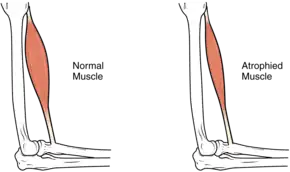

In the long term, the loss of muscle function can have additional effects from disuse, including atrophy of the muscle. Immobility can lead to pressure sores, particularly in bony areas, requiring precautions such as extra cushioning and turning in bed every two hours (in the acute setting) to relieve pressure.[24] In the long term, people in wheelchairs must shift periodically to relieve pressure.[25] Another complication is pain, including nociceptive pain (indication of potential or actual tissue damage) and neuropathic pain, when nerves affected by damage convey erroneous pain signals in the absence of noxious stimuli.[26] Spasticity, the uncontrollable tensing of muscles below the level of injury, occurs in 65–78% of chronic SCI.[27] It results from lack of input from the brain that quells muscle responses to stretch reflexes.[28] It can be treated with drugs and physical therapy.[28] Spasticity increases the risk of contractures (shortening of muscles, tendons, or ligaments that result from lack of use of a limb); this problem can be prevented by moving the limb through its full range of motion multiple times a day.[29] Another problem lack of mobility can cause is loss of bone density and changes in bone structure.[30][31] Loss of bone density (bone demineralization), thought to be due to lack of input from weakened or paralysed muscles, can increase the risk of fractures.[32] Conversely, a poorly understood phenomenon is the overgrowth of bone tissue in soft tissue areas, called heterotopic ossification.[33] It occurs below the level of injury, possibly as a result of inflammation, and happens to a clinically significant extent in 27% of people.[33]